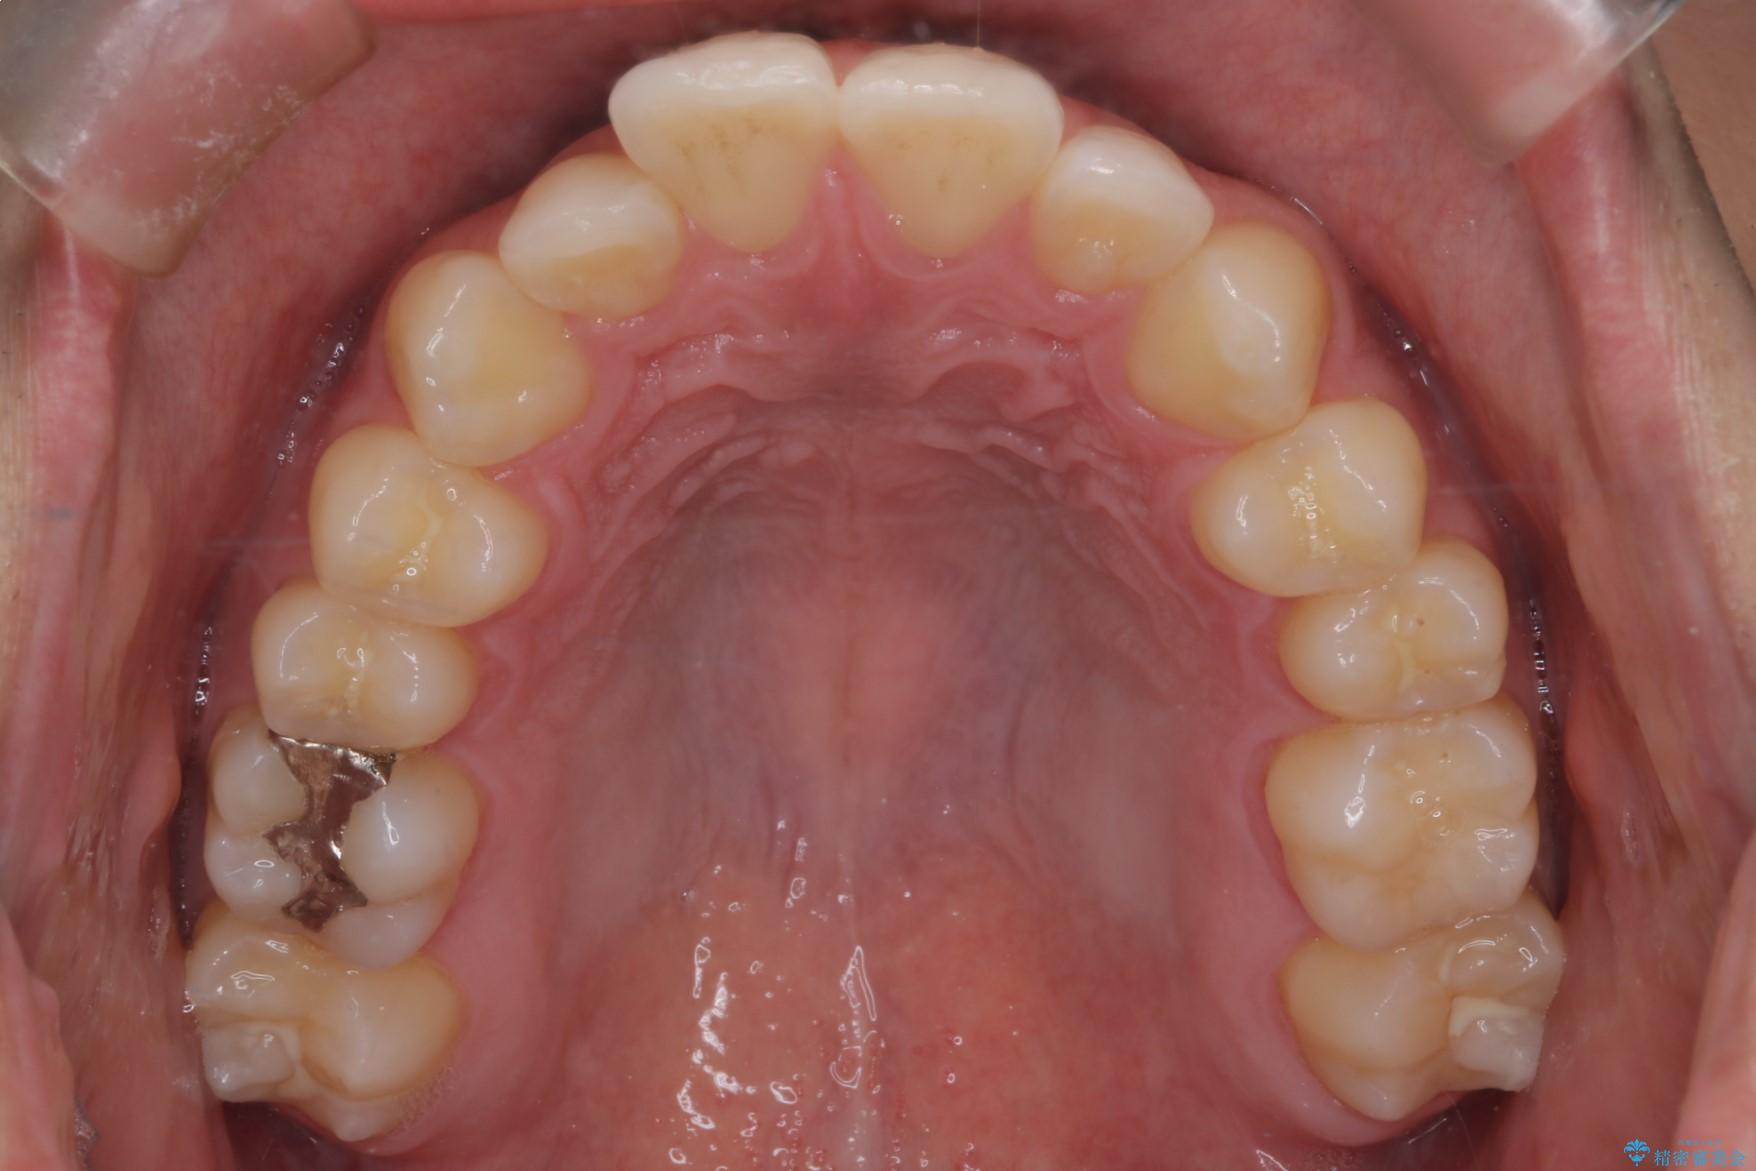

上の前歯が出ているのが気になるとご来院された患者様です。

IPR(歯と歯の間を削る処置)を行うことで、前歯の位置とがたつき整える治療計画を立てました。